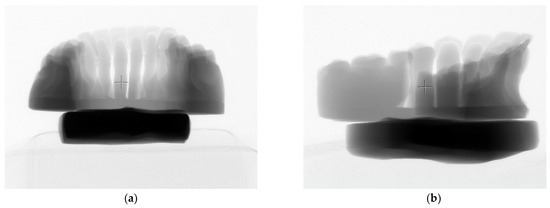

Objectives: The aim of this study was to present and describe a digital workflow integrating Digital Smile Design (DSD) with computer-aided design/computer-aided manufacturing (CAD/CAM) and additive manufacturing technologies for the fabrication of dental preparation guides, focusing on workflow feasibility, design reproducibility, and [...] Read more.

Objectives: The aim of this study was to present and describe a digital workflow integrating Digital Smile Design (DSD) with computer-aided design/computer-aided manufacturing (CAD/CAM) and additive manufacturing technologies for the fabrication of dental preparation guides, focusing on workflow feasibility, design reproducibility, and clinical handling. Materials and Methods: A digital workflow was implemented using intraoral scanning and Exocad DentalCAD 3.1 Elefsina software to design dental preparation guides based on digitally planned restorations. Preparation margins, insertion paths, and minimal material thickness were defined virtually. The guides were fabricated using both subtractive (PMMA milling) and additive (stereolithographic-based 3D printing) manufacturing techniques. Post-processing included chemical cleaning, support removal, additional light curing, and manual finishing. The evaluation was qualitative and descriptive, based on visual inspection, workflow performance, and guide adaptation to printed models. Results: The proposed digital workflow was associated with consistent fabrication of preparation guides and predictable transfer of the virtual design to the manufactured guides. Digital planning facilitated clear visualization of preparation margins and insertion axes, supporting controlled and minimally invasive tooth preparation. The workflow demonstrated good reproducibility and efficient communication between clinician and dental technician. No quantitative measurements or statistical analyses were performed. Conclusions: Within the limitations of this qualitative feasibility study, the integration of DSD with CAD/CAM and 3D printing technologies represents a viable digital approach for designing and fabricating dental preparation guides. The workflow shows potential for improving predictability and communication in restorative dentistry. Full article